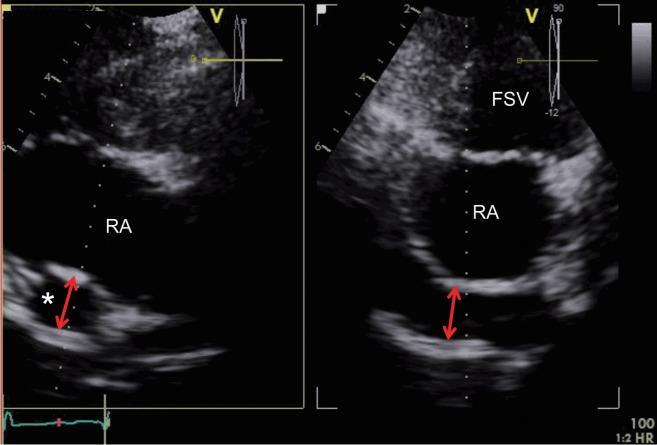

Congenital heart disease (CHD) is now more common in adults than in children due to improvements in fetal echo, neonatal and pediatric care, and surgical techniques leading to dramatically increased survivability into adulthood. Adult patients with CHD, regardless of prior cardiac surgery, experience further cardiac problems or therapeutic challenges; therefore, a non-invasive, easily accessible echocardiographic examination is an essential follow-up tool. Among echocardiographic modalities, three-dimensional (3D) echocardiography provides better delineation of spatial relationships in complex cardiac geometries and more accurate volumetric information without geometric assumptions. For atrial septal defects, an en face view of the tissue defect allows better decisions on device closure. For tricuspid valve malformations, an en face view provides diagnostic information that is difficult to obtain from routine 2D tomography. In repaired tetralogy of fallot with pulmonary regurgitation, preoperative 3D echocardiography- based right ventricular volume may be used to determine the timing of a pulmonary valve replacement in conjunction with cardiovascular magnetic imaging. For optimal adult CHD care, 3D echocardiography is an important complement to routine 2D echocardiography.

由于胎儿超声心动图、新生儿及儿科护理以及手术技术的进步,先天性心脏病(CHD)在成人中比在儿童中更为常见,这使得成年后的生存率显著提高。患有CHD的成年患者,无论之前是否接受过心脏手术,都会面临进一步的心脏问题或治疗挑战;因此,一种无创、易于进行的超声心动图检查是必不可少的随访工具。在超声心动图检查方式中,三维(3D)超声心动图能够更好地描绘复杂心脏结构中的空间关系,并且无需进行几何假设就能提供更准确的容积信息。对于房间隔缺损,组织缺损的正面视图有助于更好地决定封堵装置的使用。对于三尖瓣畸形,正面视图可提供从常规二维断层扫描难以获得的诊断信息。在修复后伴有肺动脉反流的法洛四联症中,术前基于三维超声心动图的右心室容积可与心血管磁共振成像结合使用,以确定肺动脉瓣置换的时机。为了实现对成年CHD患者的最佳护理,三维超声心动图是常规二维超声心动图的重要补充。